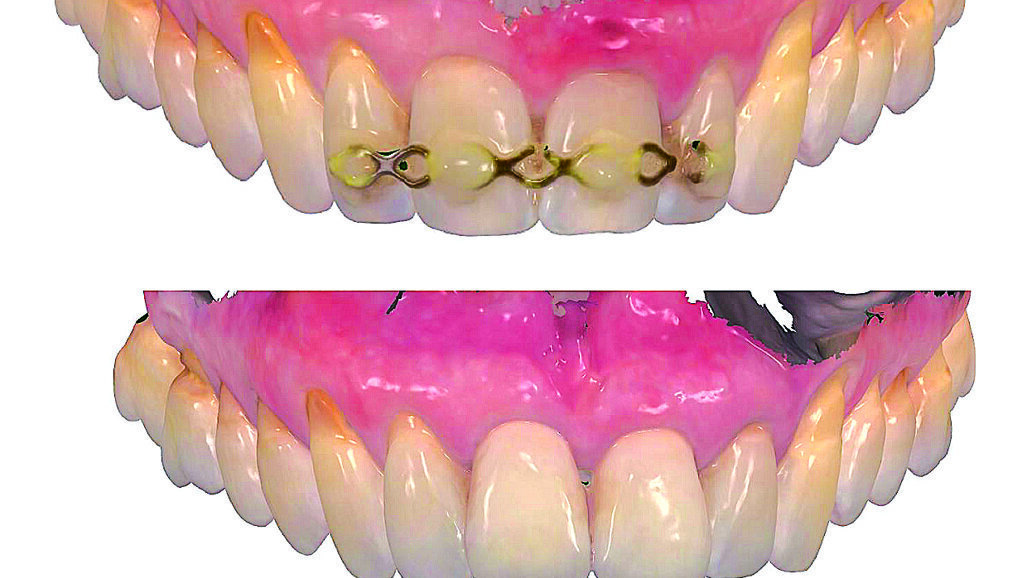

Slika 1. Početna situacija: Frontalni prikaz reponiranih i splintiranih zubi 11 i 21

Slika 13.a i b: Usporedba profila mekog tkiva prije (gore) i poslije (ispod) implantacije s pomoću intraoralnog skena

Slika 14. Usporedba tijeka gingive prije (gore) i poslije (dolje) implantacije s pomoću intraoralnog skena